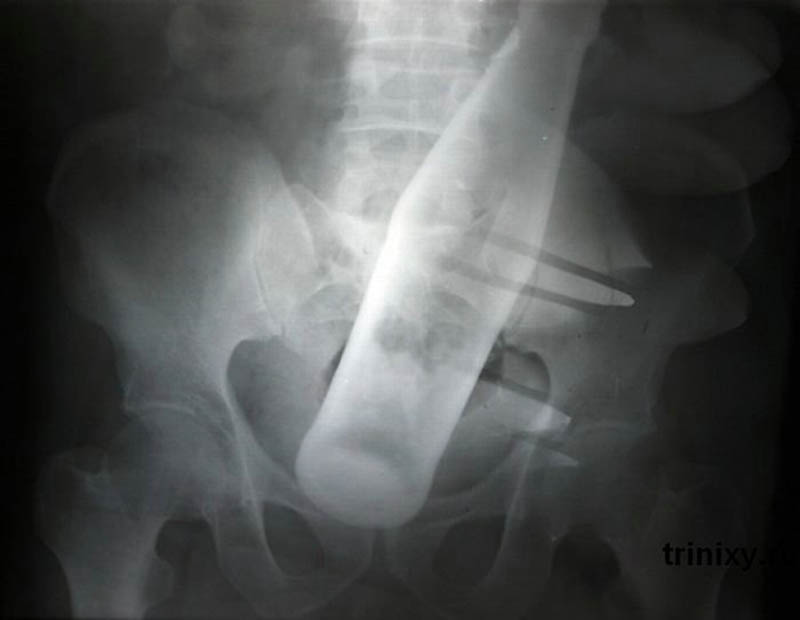

Бутылка из-под «Пепси» в анусе 60-летнего мужчины